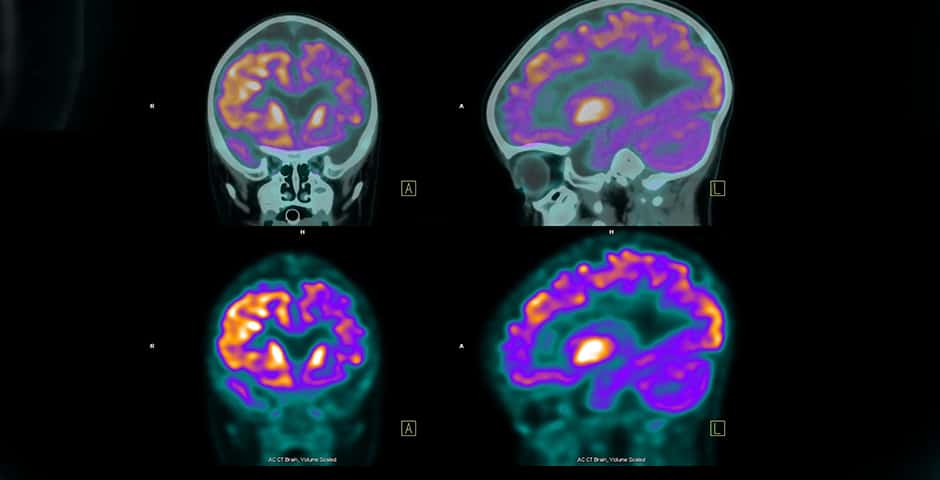

Jag arbetar med positron emission tomografi (PET), som är en avbildningsteknik för att studera hjärnans kemi hos levande individer. En viktig tillämpning av PET är att studera de neurokemiska avvikelser som ligger till grund för depression, samt att undersöka hur antidepressiva läkemedel påverkar hjärnan. De här skillnaderna tenderar dock att vara små och subtila och kräver noggranna studier för att vi ska kunna hitta och förstå dem.

Med hjälp av nya framsteg inom statistik och den höga prestandan hos moderna datorer kommer jag att utveckla ett helt nytt sätt att kvantifiera PET-data. Det bör avsevärt förbättra PET: s förmåga att upptäcka och beskriva de här små förändringarna. Jag kommer först att validera metoden och sedan tillämpa den på både stora befintliga datamängder, och på nyligen insamlade PET-data från patienter med depression. Jag kommer också att undersöka de neurokemiska förändringar som antidepressiva läkemedel ger upphov till. Med hjälp av den här metoden hoppas vi kunna kasta nytt ljus över depressionens neurokemi.